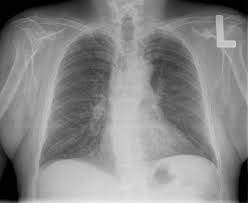

Dalam ilmu kedokteran, sinar-x dapat digunakan melihat kondisi tulang,gigi serta organ tubuh yang lain tanpa melakukan pembedahan langsung ke tubuh pasien.

Dikenal beberapa posisi dalam foto Rontgen (radiologi) kedokteran :

- PA (Postero-Anterior) sumber cahaya berada di belakang pasien, dan plat hitam berada di depan pasien. Posisi ini yang paling sering digunakan terutama untuk foto Rontgen thorax (dada)

- AP (Anterior-Postero) Sumber cahaya berada di depa pasien, dan plat hitam berada di belakang pasien. Posisi ini biasa digunakan pada pasien yang tidak mampu berdiri unuk mengambil posisi PA karna sakit yang dideritanya.

- Lateral (samping)